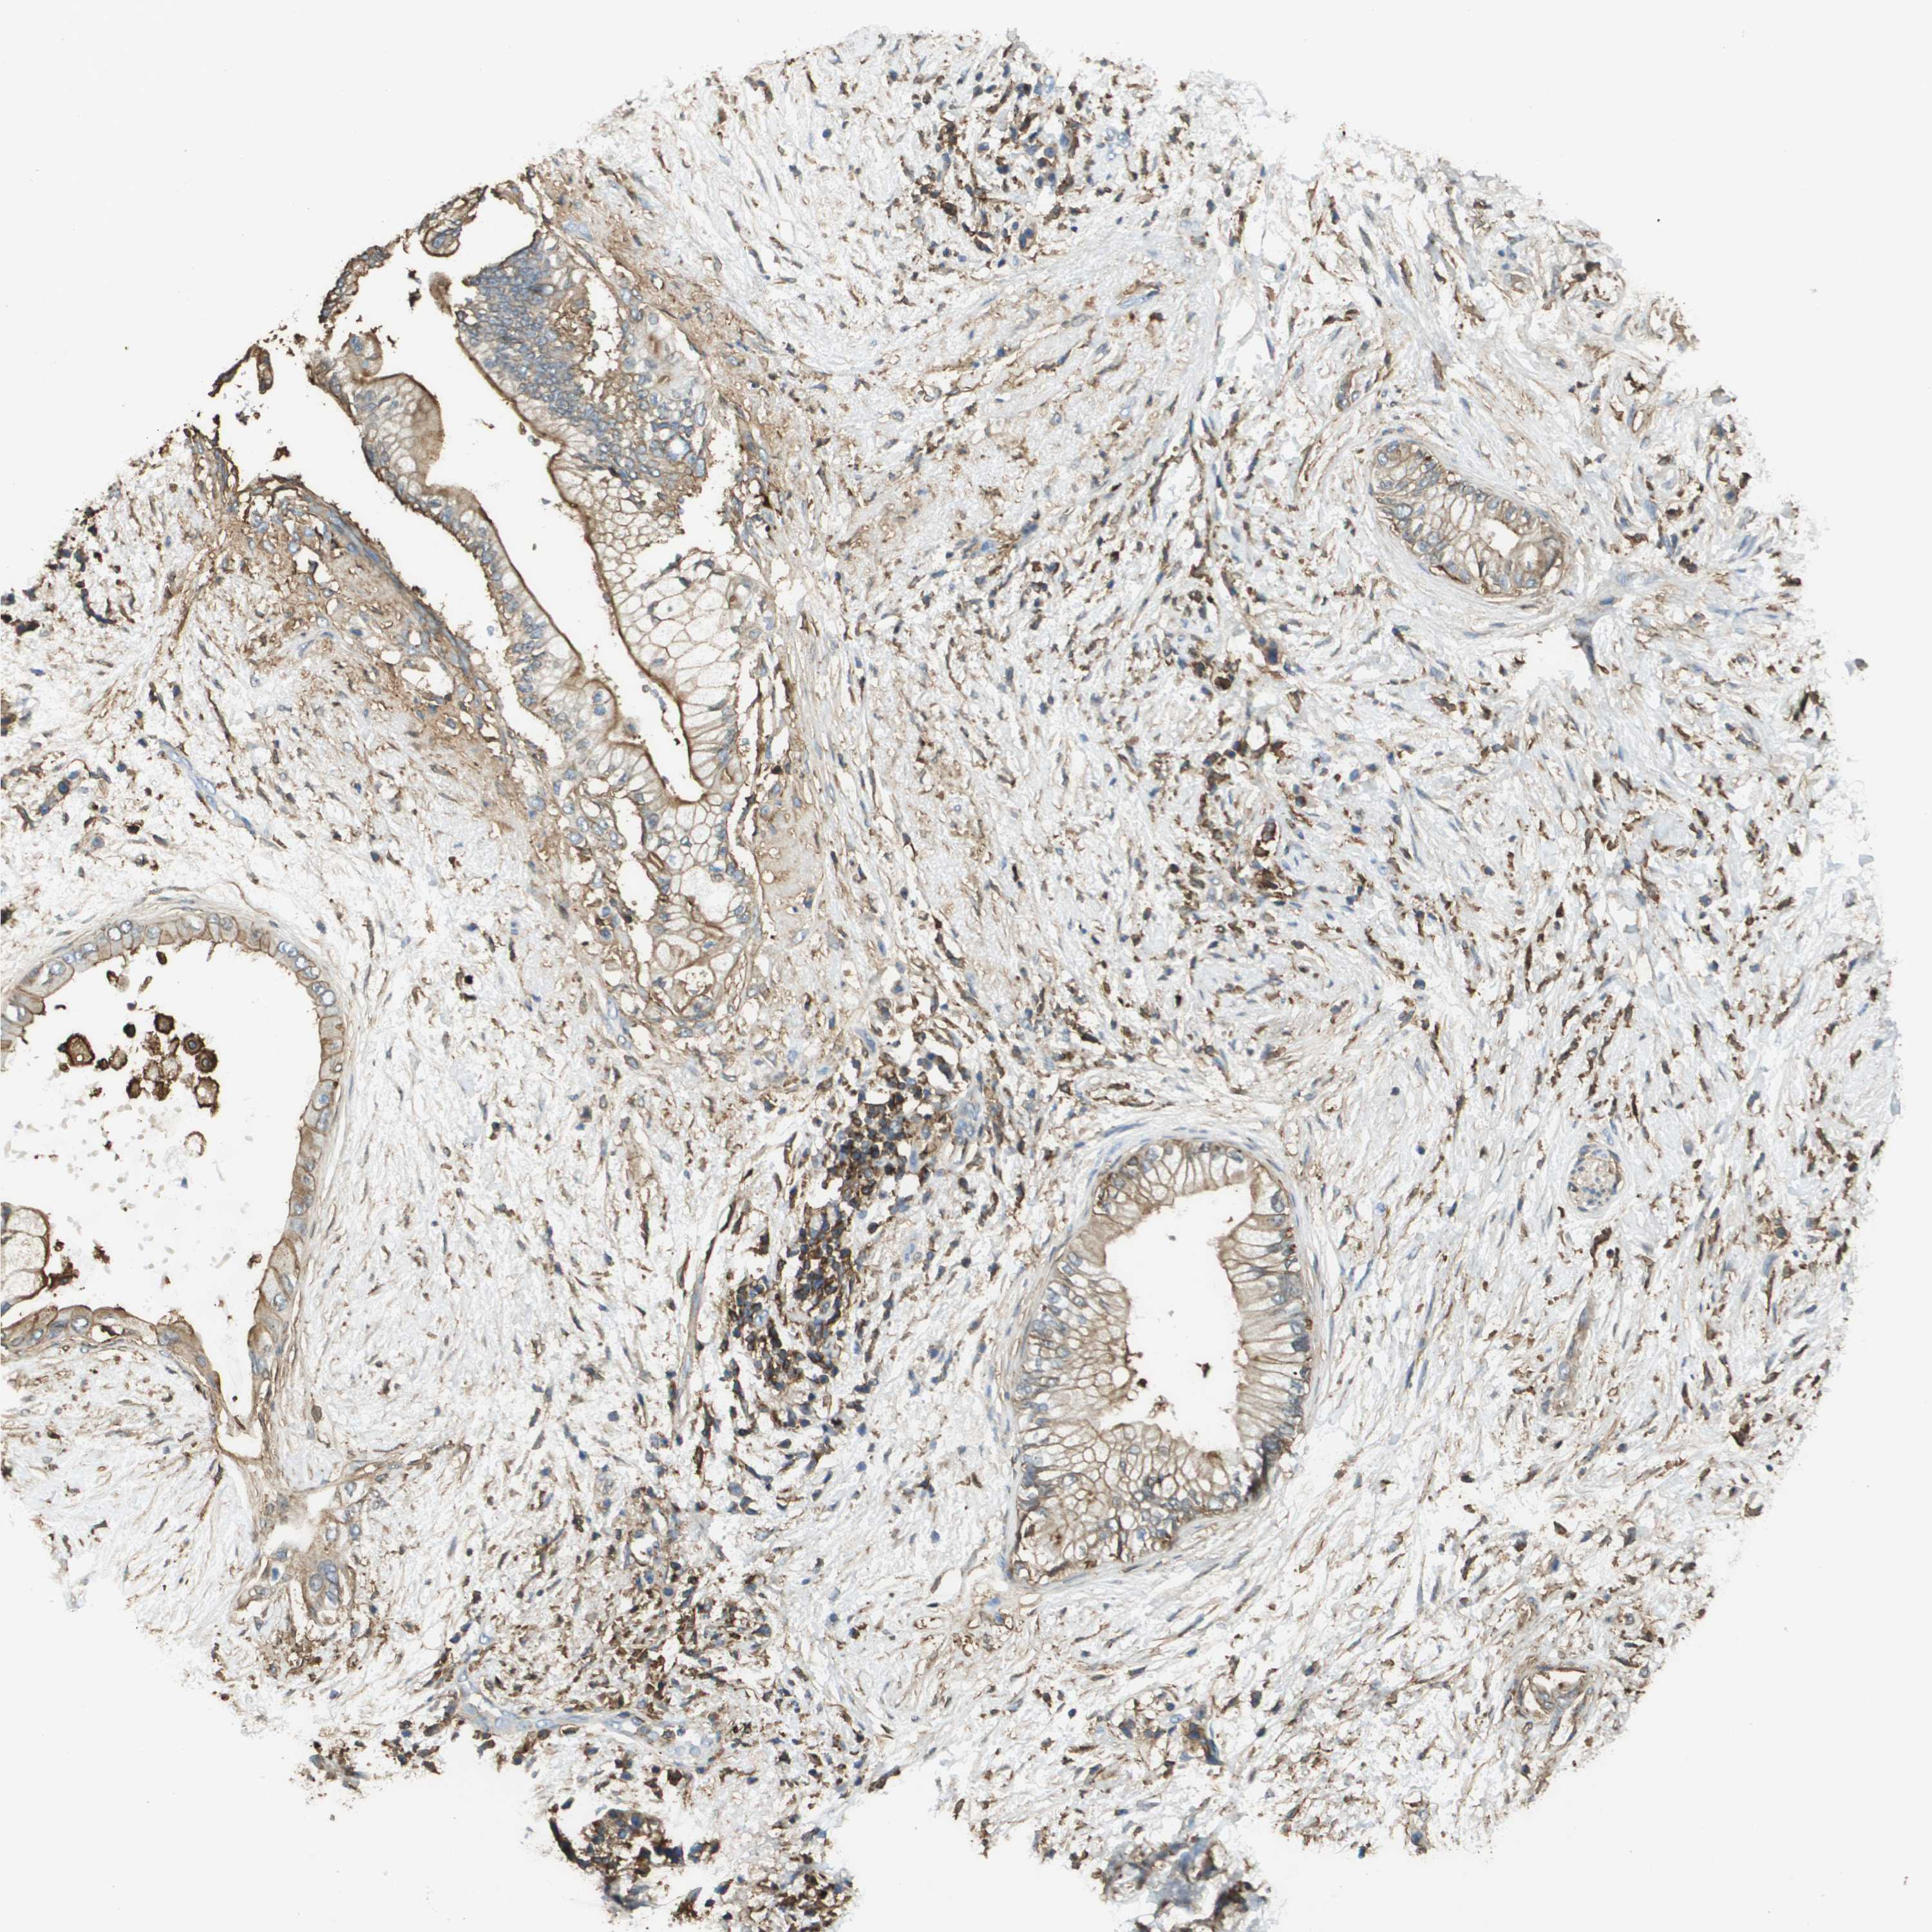

PANCREATIC CANCER - Protein expressioni

A mouse-over function shows sample information and annotation data. Click on an image to view it in a full screen mode. Samples can be filtered based on level of antibody staining by selecting one or several of the following categories: high, medium, low and not detected. The assay and annotation is described here.

Note that samples used for immunohistochemistry by the Human Protein Atlas do not correspond to samples in the TCGA dataset.

Antibody stainingi

Antibody staining in the annotated cell types in the current human tissue is reported as not detected, low, medium, or high, based on conventional immunohistochemistry profiling in selected tissues. This score is based on the combination of the staining intensity and fraction of stained cells.

Each image is clickable and will lead to virtual microscopy that enables deeper exploration of all samples and also displays staining intensity scores, fraction scores and subcellular localization as well as patient and tissue information for each sample.

Antibody HPA016450

Antibody HPA021079

Staining

High

Medium

Low

Not detected

Intensity

Strong

Moderate

Weak

Negative

Quantity

>75%

75%-25%

<25%

None

Location

Nuclear

Cytoplasmic/membranous

Cytoplasmic/membranous,nuclear

Adenocarcinoma, NOS